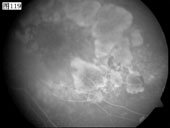

优秀眼底图片奖应征作品展示

17 18 19 20